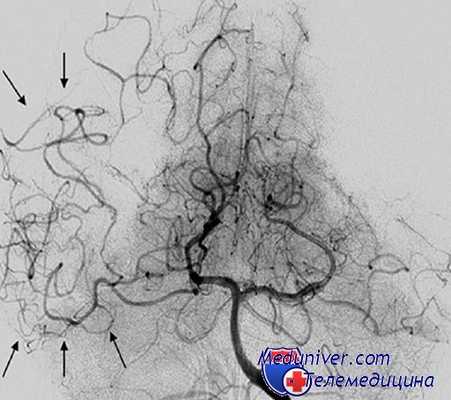

На основании дооперационной ангиографической картины, анализа геометрии аневризм мы разделили их на мешотчатые, фузиформные (веретенообразные) и «фузиформноподобные» аневризмы (рис. 1).

Рис. 1. Виды аневризм: А — мешотчатая, Б — фузиформная, В — фузиформноподобная

К фузиформноподобным мы отнесли те случаи, когда ветви СМА были вовлечены в структуру шейки или отходили непосредственно от мешка аневризмы, что снижало радикальность операции и повышало риски развития как интра-, так и послеоперационных осложнений (рис. 2).

Рис. 2. Распределение аневризм по типу строения